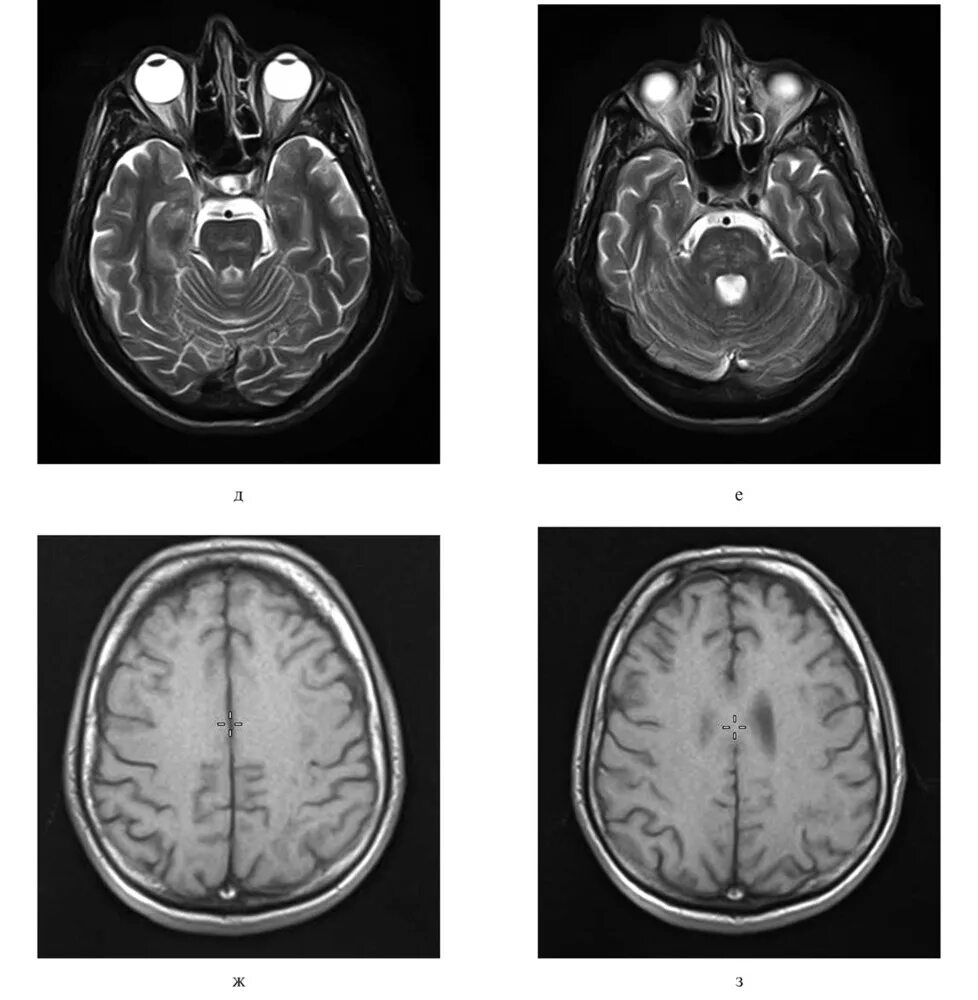

Т2 гипоинтенсивный